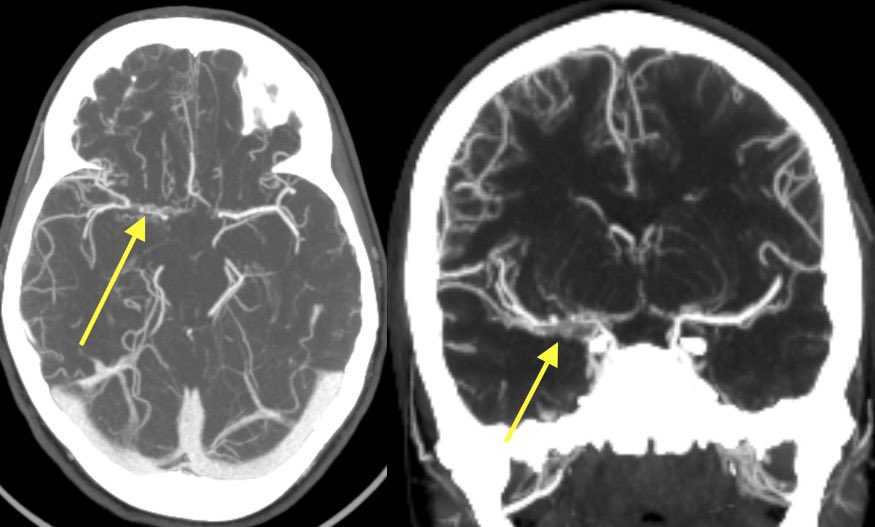

Imaging of Moyamoya disease/syndrome Imaging: Thread-like intracranial ICA/MCA with attenuated branches and “puff of smoke” appearance on DSA Co